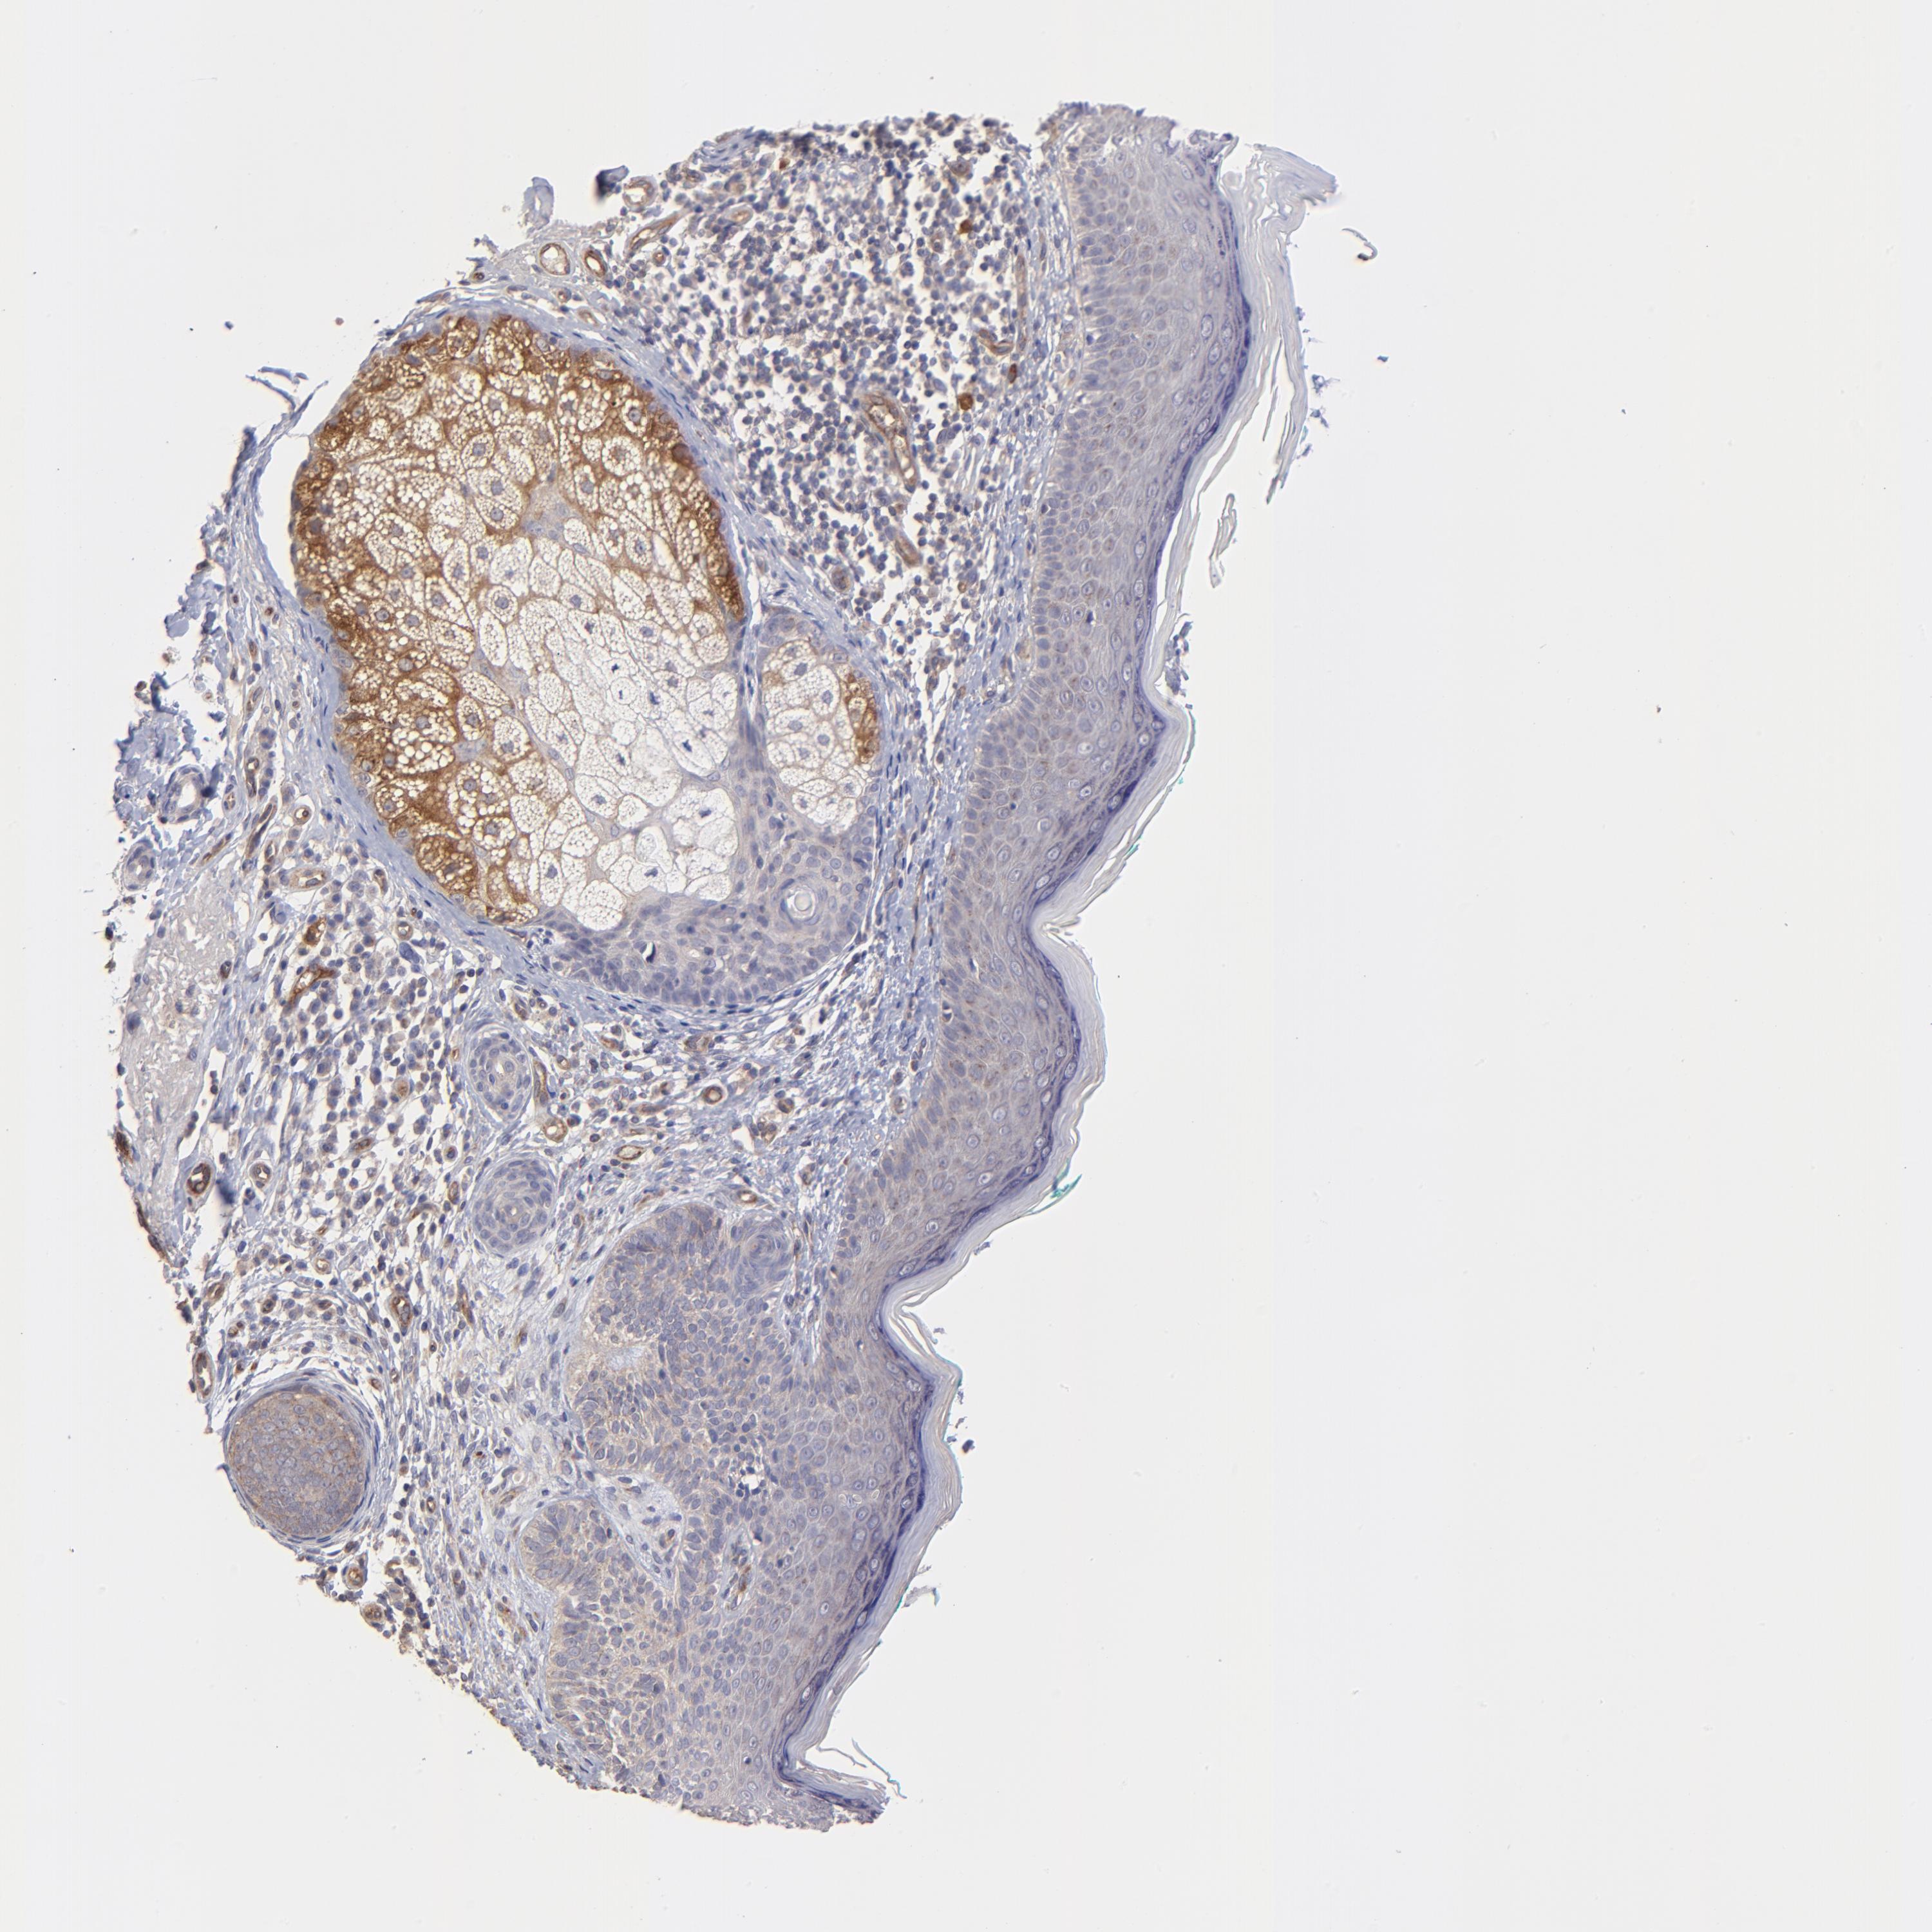

SKIN CANCER - Protein expressioni

A mouse-over function shows sample information and annotation data. Click on an image to view it in a full screen mode. Samples can be filtered based on level of antibody staining by selecting one or several of the following categories: high, medium, low and not detected. The assay and annotation is described here.

Antibody stainingi

Antibody staining in the annotated cell types in the current human tissue is reported as not detected, low, medium, or high, based on conventional immunohistochemistry profiling in selected tissues. This score is based on the combination of the staining intensity and fraction of stained cells.

Each image is clickable and will lead to virtual microscopy that enables deeper exploration of all samples and also displays staining intensity scores, fraction scores and subcellular localization as well as patient and tissue information for each sample.

Antibody HPA003300

Squamous cell carcinoma, NOS

Basal cell carcinoma